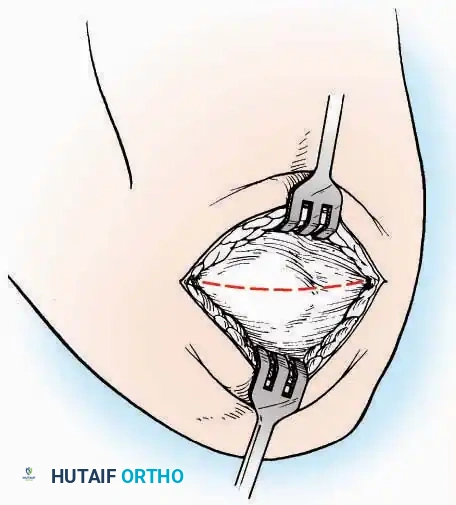

Medial Approach

Indications: Hallux valgus correction (bunionectomy), first MTP arthrodesis, or cheilectomy.

Surgical Technique:

* Incision: Make a curved incision 5 cm long on the medial aspect of the joint. Begin just proximal to the IP joint, curve it over the dorsum of the MTP joint (medial to the extensor hallucis longus [EHL] tendon), and terminate on the medial aspect of the first metatarsal 2.5 cm proximal to the joint.

* Superficial Dissection: As the deep fascia is incised, identify and laterally retract the medial branch of the first dorsal metatarsal artery and the medial branch of the dorsomedial nerve (a terminal branch of the superficial peroneal nerve).

* Deep Dissection: Dissect the fascia from the dorsum down to the bursa overlying the medial eminence of the metatarsal head.

* Capsulotomy: Make a curved incision through the bursa and joint capsule. Begin dorsomedially, continue proximally dorsal to the metatarsal head, sweep plantarward, and end distally on the medioplantar aspect of the joint. This creates an elliptical, racquet-shaped flap attached at the base of the proximal phalanx.

⚠️ Surgical Pitfall

While distal reflection of this racquet flap provides ample exposure of the first MTP joint, the extensive subfascial undermining required can compromise the vascularity of the skin flap, leading to delayed healing or necrosis. Consequently, the dorsomedial approach is often preferred in modern practice.